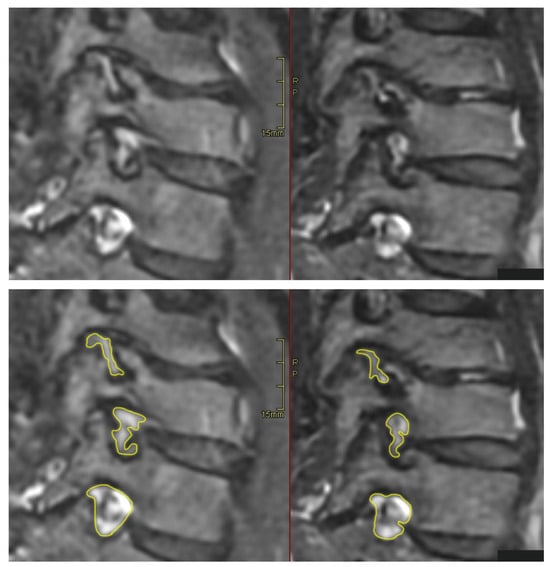

All patients were positioned without any complaints in the DMRICS apparatus, outside the MRI gantry. The patients were subsequently positioned within the MRI for a relaxed image acquisition. After successfully conducting the simulated Spurling test, immediate imaging was performed, which produced clinically acceptable image quality in 9 out of 10 patients in both relaxed and provoked positions, as shown in Figure 2 and Figure 3.

The significant increase in the qualitative gradings of the foramina when comparing MRI before and during the simulated Spurling test indicates that a Spurling test leads to higher Park and Kim grades. This offers not only insights into the variations of the often-employed clinical Spurling test but also suggests a possible clinical utility for dynamic MRI. The method could help in determining the severity of foraminal stenosis and identifying the impacted nerve roots if they are not distinctly discernible in a routine, relaxed MRI, especially when several foramina are narrow on a routine MRI and the symptoms and clinical examination cannot discriminate which nerve root(s) are giving rise to the experienced pain. However, for the foraminal area and cross-distance measures, no significant changes were detected in the present work. The reason for these contradictory findings may be that the foraminal shape shifts with compression and thereby the nerve compression may increase, even if the overall area is not changed or even increases; see Figure 2 and Figure 3. Further, the magnitude of measurement error in such small structures, especially for the axial-cross-distance measurements may also play a role here.

Figure 3. The (left) image shows the transverse plane in a relaxed position compared with the (right) image taken during the Spurling test.